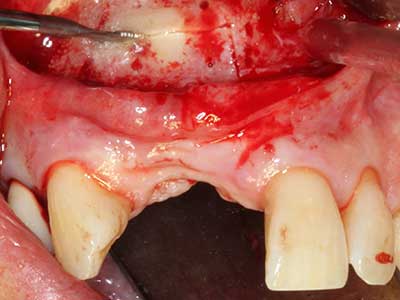

When surgical procedures are performed on bone in the immediate vicinity of sensitive structures such as blood vessels or nerves, rotary instruments pose a significant risk of iatrogenic injury. Piezoelectric devices can be helpful for preparation of bone covers and removal of hard tissue close to nerves, particularly for exposure of nerves after iatrogenic injury but also during nerve lateralization for resective and reconstructive procedures or implant placement (Fig. 17-20). Light contact between the piezotip and the nerve does not generally result in damage but proceeding incautiously with saw-like motions or attachments where a residual bone substrate remains may cause temporary or even permanent nerve damage. However, the risk of damage is considered to be substantially lower than when using saws or milling instruments (Pereira, Gealh et al. 2014).

Fig. 18: Preparation of a cortical cover with the piezo bone saw (Piezomed, W&H).

Fig. 19: Surgical site after neurolysis and removal of osteoma.

Fig. 20: The removed bone cover is re-adapted and fixed with an osteosynthesis screw (KLS Martin, Tuttlingen).